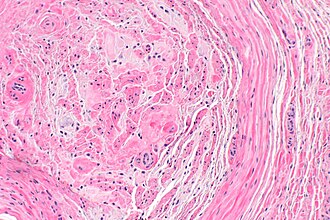

Template:Px Morton neuroma. H&E stain. | |

| LM | extensive fibrosis around and within the nerve, digital artery +/-thrombosis +/-arterial thickening |

- Extensive fibrosis around and within the nerve.

- Digital artery:

- +/-Thrombosis.

- +/-Arterial thickening.

The sections show soft tissue with larger nerves with extensive fibrosis around and within the nerve. There is no significant nuclear atypia. Mitotic activity is not readily apparent.